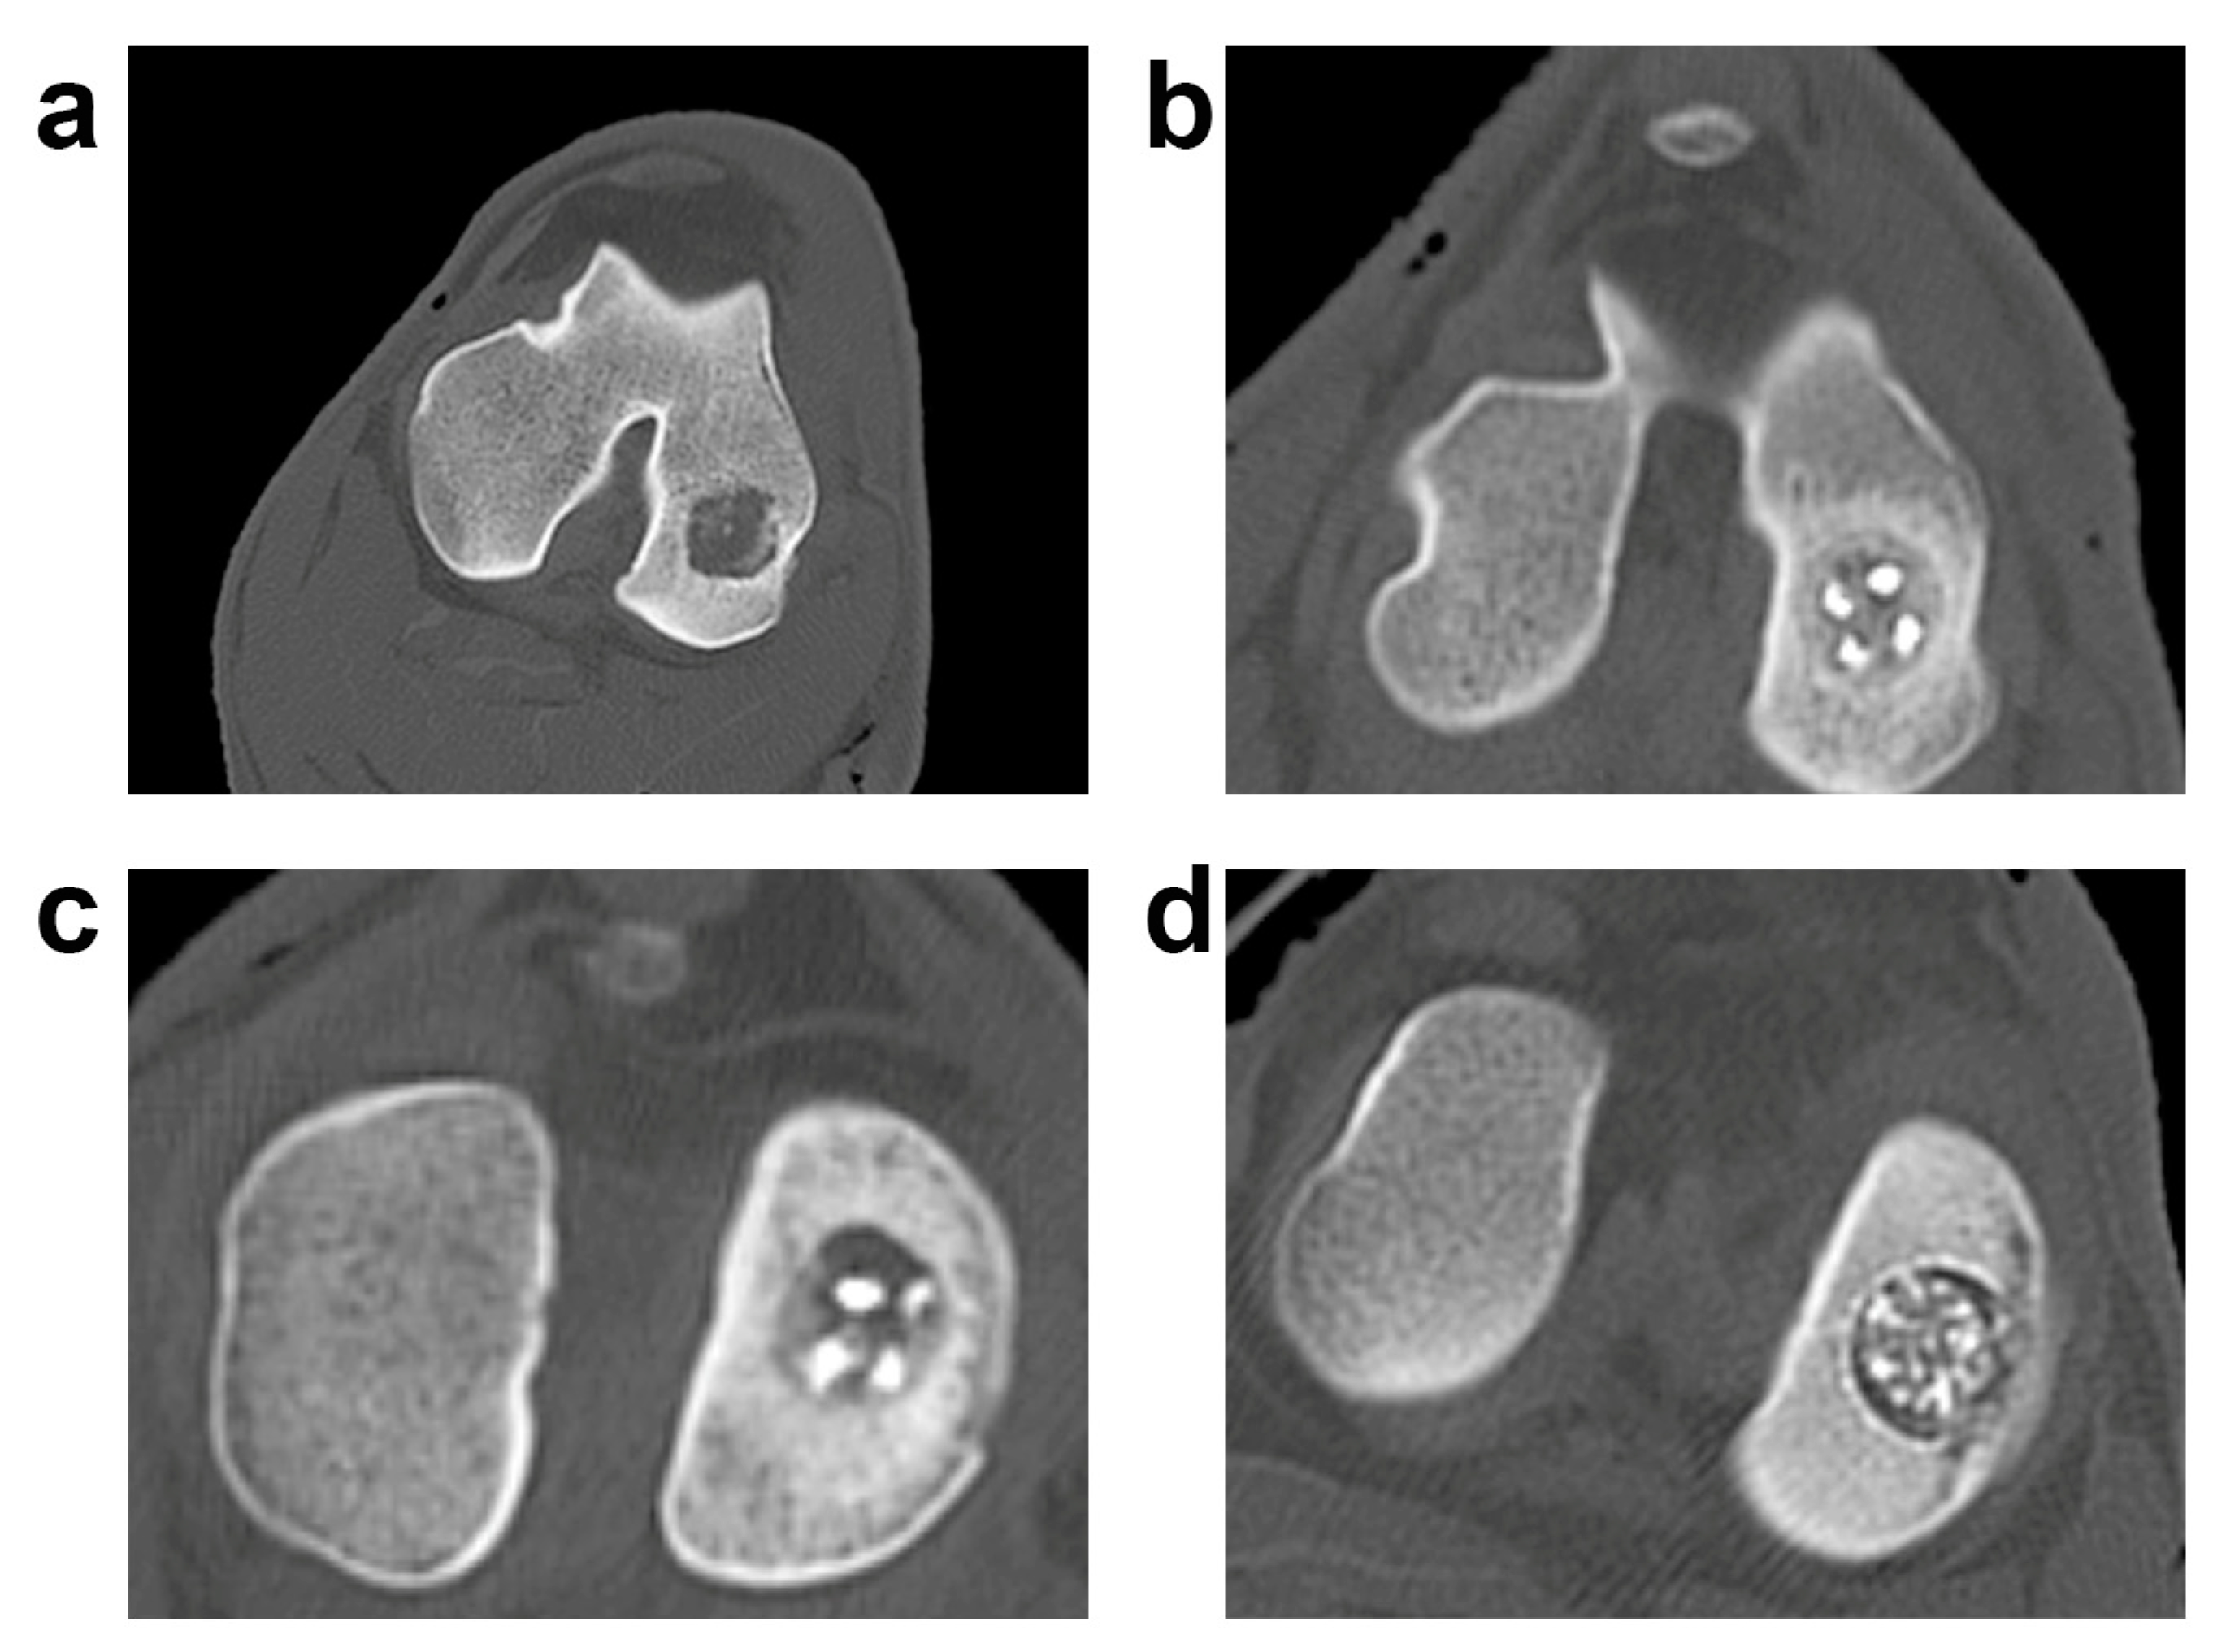

CT scans showed the persistence of the bony scaffold, well integrated with the surrounding bone as shown in our previous publication [39] (Figure 6).

Figure 6.

CT evaluation of the three biphasic scaffolds. (a) Radiologic pictures of the experimental groups; a representative lesion for each experimental group is shown. Control (CTRL): (a); HMG: (b); HWS: (c); BWS: (d).